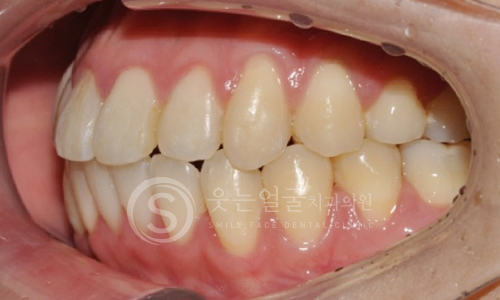

한눈에 보는

임플란트 전후사진